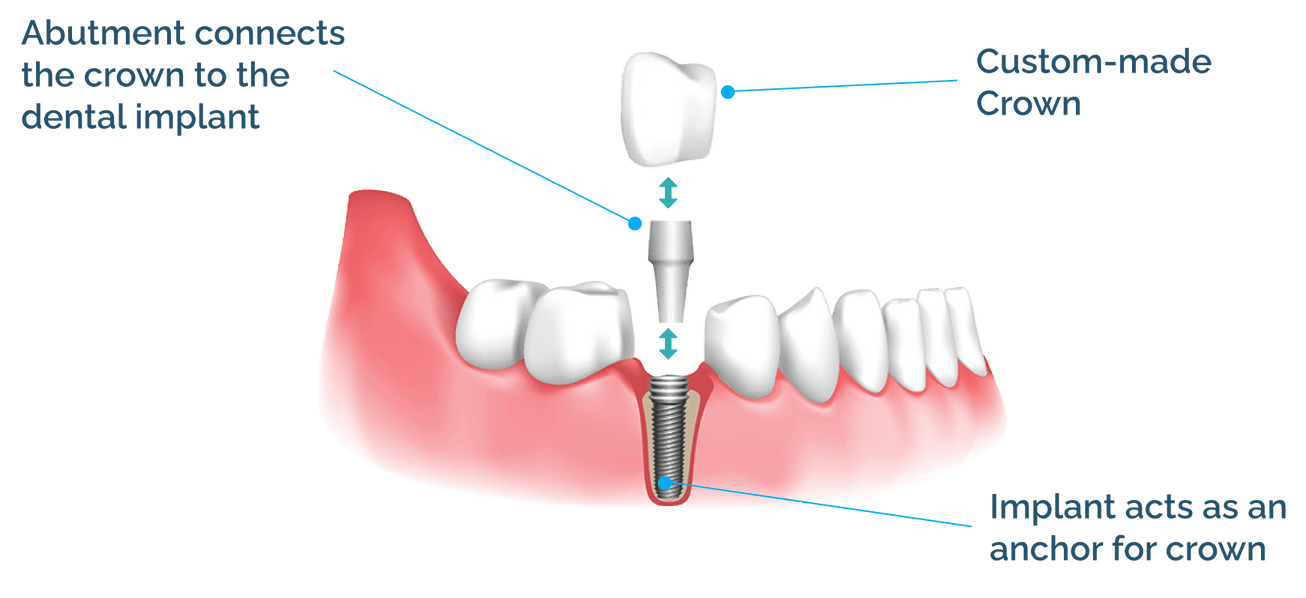

Dental implants are most modern treatments that restores a missing tooth in a fixed manner. |

Implants are longterm fixed artificial tooth fixed dentures that mimic the original tooth structure. It is a treatment in which a titanium implant is attached to the bone and with its help a tooth or bridge is placed like a real tooth. It will last a lifetime if properly cared for. |

Next a small titanium (root implant) is inserted to the jaw bone or the extracted socket and wait to heal it.options for immediate tooth fixing are available now. |

An extender called abutment is placed to the root implant. It is used to connect the implant root with the implant crown.There are systems with single piece implants which can be loaded with teeth in 3 days. |

If one or few teeth needs replacement then the crown is screwed or cemented to the implant directly. In the case of complete dentures, the denture is fixed or added to a metal frame and then this frame is screwed to the implant. |